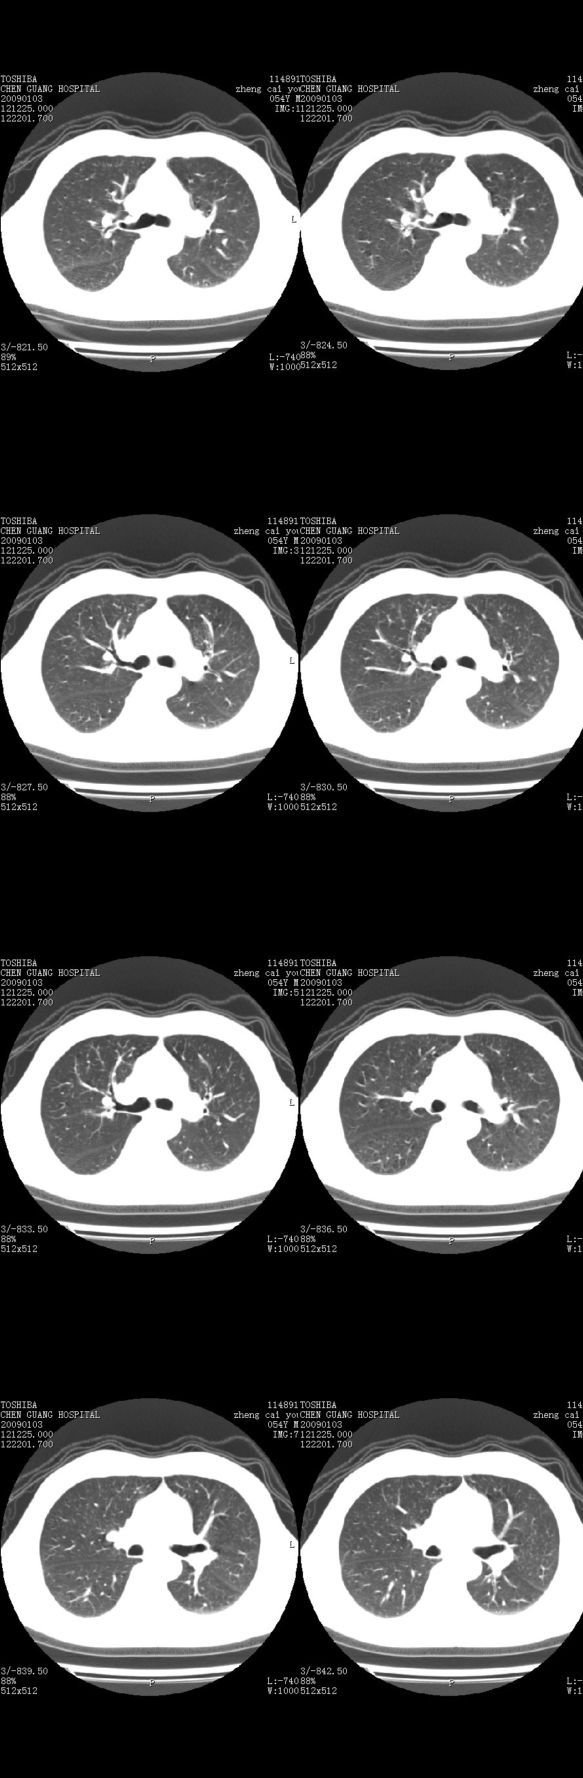

男,54岁,平时有吸烟后咳嗽、咯痰史,因右侧胸部(腋窝下)疼痛来检查平片,见右下肺动脉干起始处处结节,后到同学处做了平扫及增强。请各位老师帮忙看一下,不甚感谢!!!!!

右肺下叶支气管扩张。

考虑------支气管壁增厚---局限性气肿---建议----气管镜进一步检查

小叶中心型肺气肿

肺窗薄扫、常规扫描均未见明确病变;右下肺门圆形与肺血管等密度影,考虑为血管变异;应该要纵隔窗才能进一步明辨。

主要应该看一下纵隔窗,感觉到右肺门的血管有局限性的扩张,呈结节状,再做个增强ct扫描.